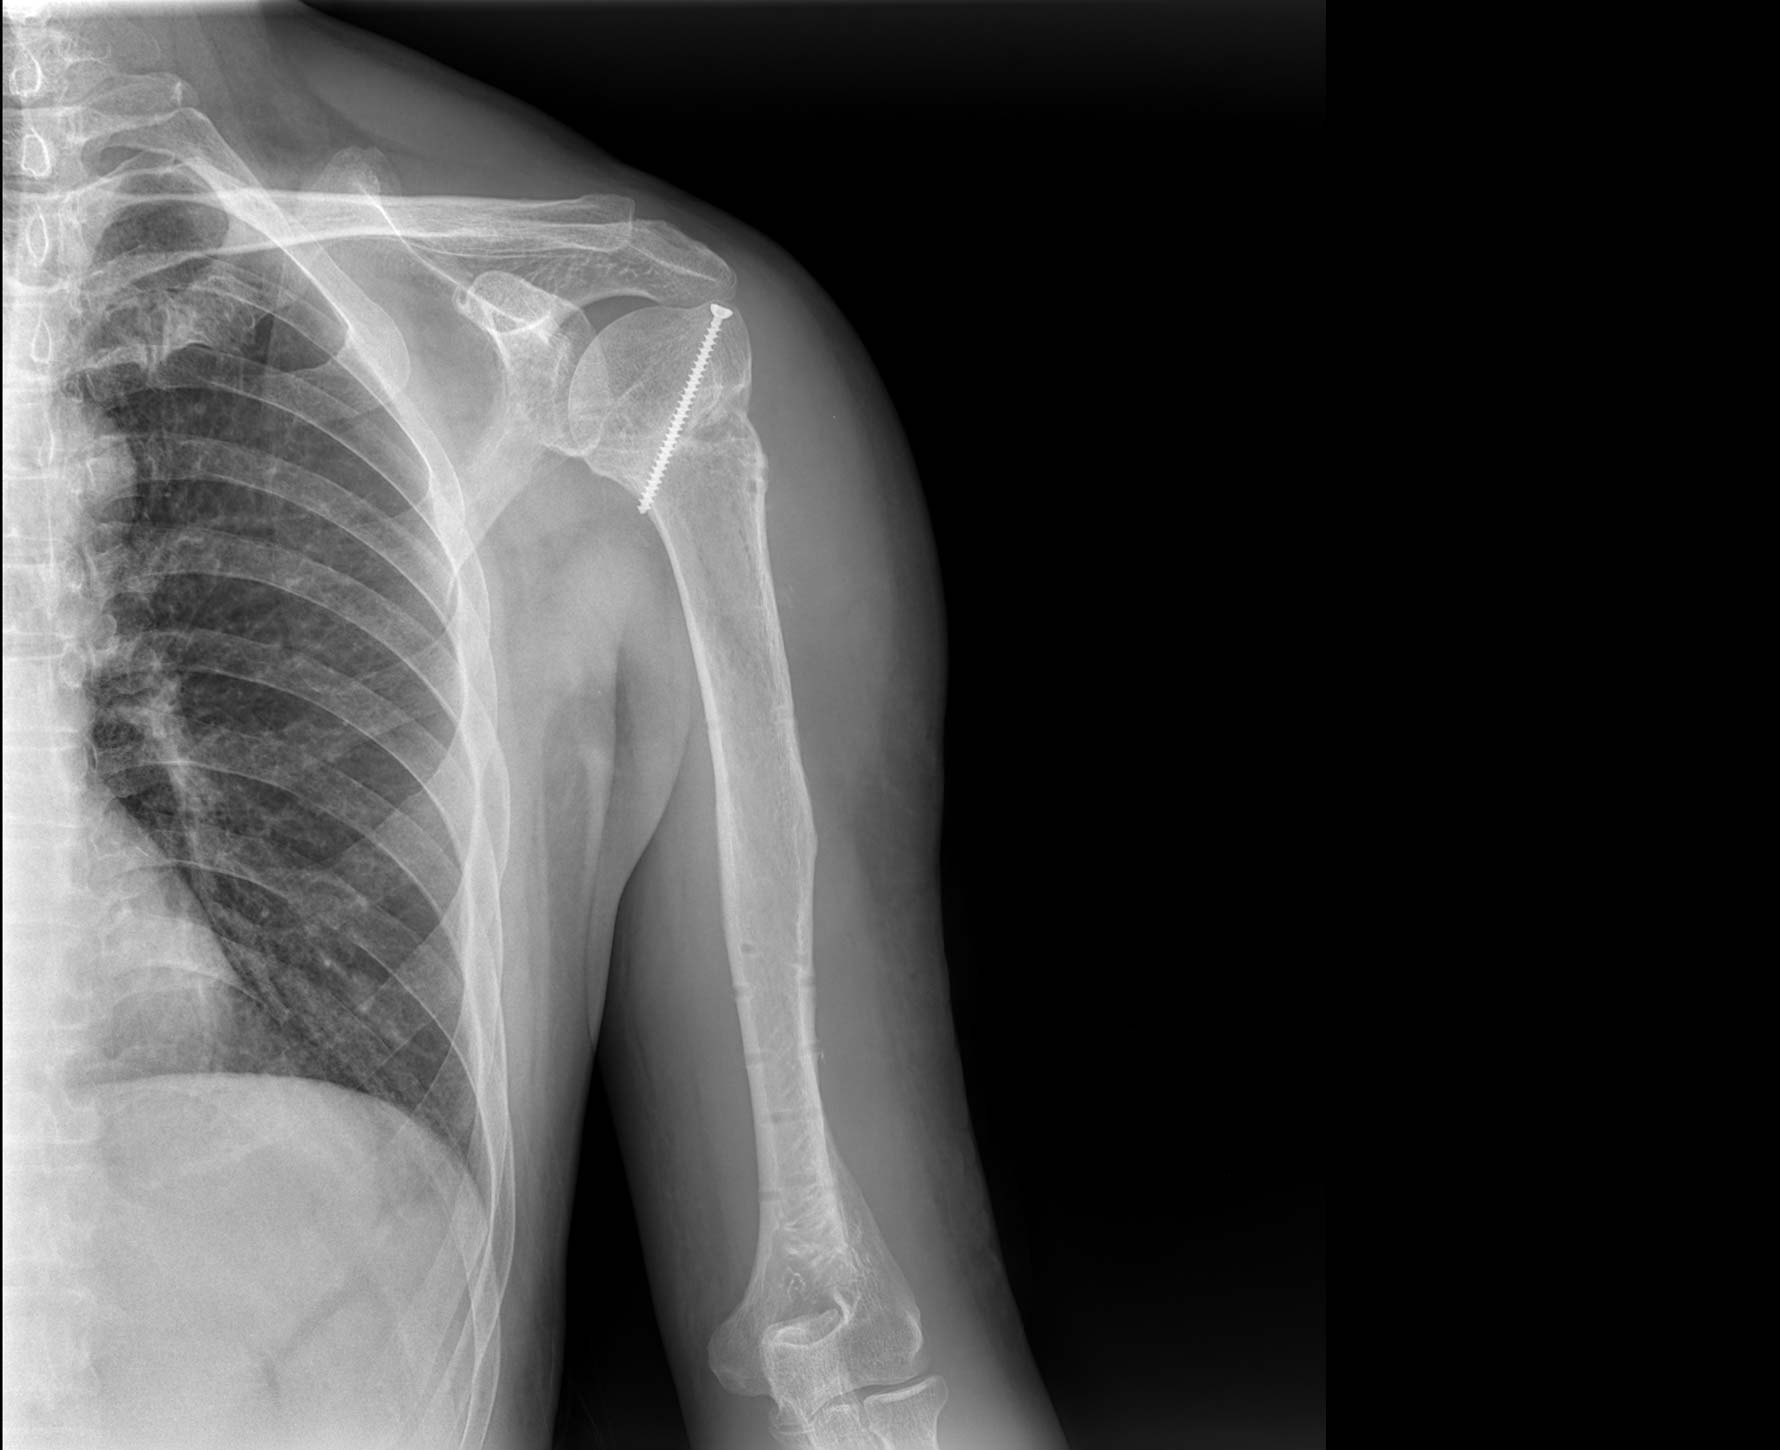

适用于全身各部位摄影

(常规摄影和特殊摄影)

适用于全身各部位摄影

(常规摄影和特殊摄影)